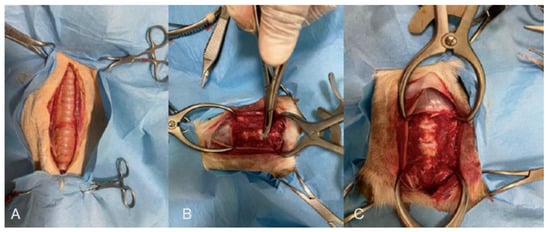

Figure 1. (A) Before, (B) during, and (C) after the ventral slot procedure to remove two intervertebral disks and the dorsal longitudinal ligament.